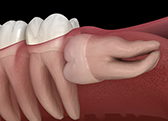

特にご自身の歯が長持ちするように虫歯や歯周病から予防することに力を入れております。